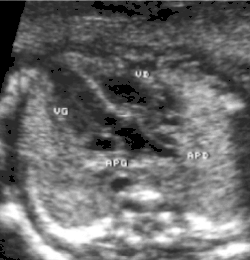

- Les coupes sous costales qui montrent bien le trajet parallèle des gros vaisseaux et leur inversion. Cet examen permettra d'éliminer en particulier un retour veineux pulmonaire anormal total bloqué qui aurait pu rendre compte de l’hypervascularisation pulmonaire sur la radiographie des poumons.

- le signe d'appel habituel est la perte du croisement des gros vaisseaux. Normalement, l'aorte et le tronc pulmonaire se croisent peu après leur sortie du cœur. Il est donc impossible de dérouler les deux vaisseaux sur un même plan de coupe. Quand l'aorte est vue longitudinalement, le tronc pulmonaire n'apparaît qu'en section transversale ("aorte en long, tronc pulmonaire en rond") et vice-versa. Dans la D-TGV simple, la plus fréquente, les vaisseaux ont un trajet parallèle et peuvent donc être visualisés longitudinalement simultanément.

- la confirmation est obtenue par l'analyse des gros vaisseaux et de leurs connexions aux ventricules. L'aorte est caractérisée par le fait qu'elle décrit une crosse, donne naissance aux vaisseaux à destinée céphalique et est le vaisseau qui monte le plus haut dans le thorax. Le tronc pulmonaire est caractérisé par sa bifurcation précoce en deux branches, les artères pulmonaires droite et gauche. Sur un cœur par ailleurs normal, le ventricule droit est situé en avant et à droite du ventricule gauche, le tronc pulmonaire est donc le vaisseau le plus antérieur. La TGV se caractérise par la position antérieure du vaisseau qui décrit la crosse et donne les vaisseaux céphaliques : l'aorte.